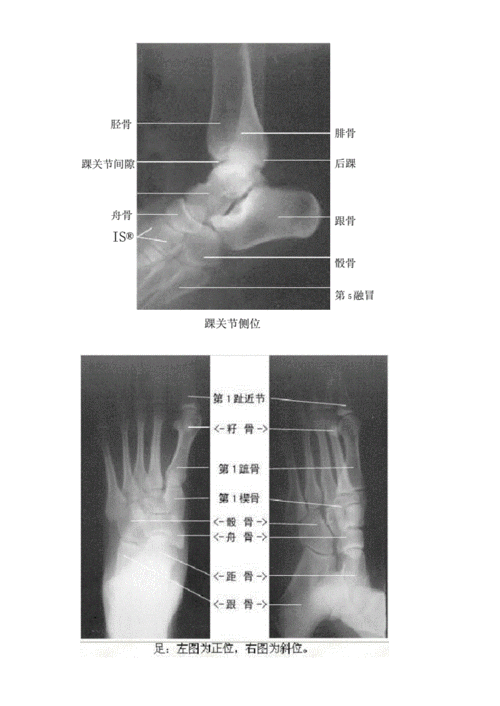

足x线解剖图,足正侧位x线解剖图

超清晰的下肢小腿踝与足解剖图

x线高清图谱 | 精致足部解剖

足正侧位x线解剖图

踝关节x线解剖

足侧位x线解剖图

踝关节x线解剖图